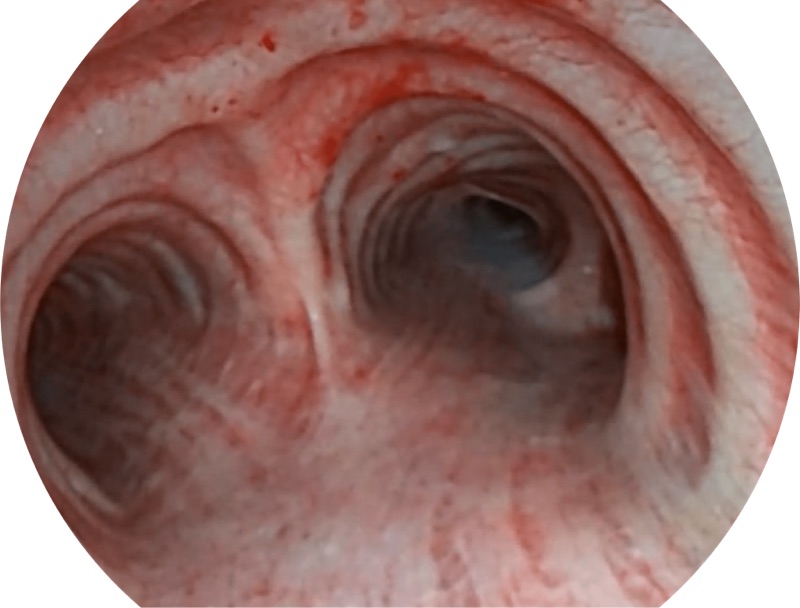

白光

SFI

VIST